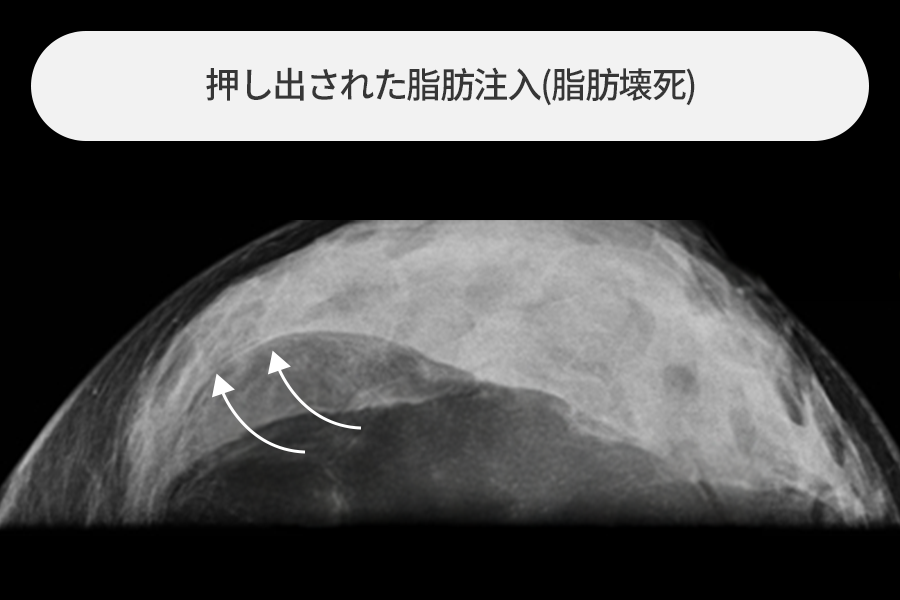

溶け出した脂肪が乳房を横切って帯を作った場合

生着できなかった脂肪壊死の塊が乳房を横切る長い帯を作り、内視鏡所見でも多量の石灰化が観察されました。

超音波や内視鏡など映像装置ガイドの下、様々な脂肪注入副作用病変を除去しました。